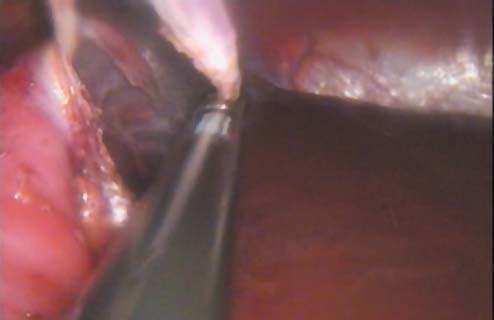

Пациентка была оперирована в положении на «здоровом» боку. Учитывая расположение висты в верхнем сегменте почки, доступ осуществлен в точке латеральнее и выше пупка. Разрез кожи 2,0 см. Порт установлен под контролем зрения. Использован прибор SILS - губчатое устройство с 3 каналами для троакаров и отдельной канюлей для инсуфляции. Установлено два 5-ти миллиметровых троакара для инструментов и 10-ти мм видеокамера (рис.2).

Рис. 2. Установка SILS порта.